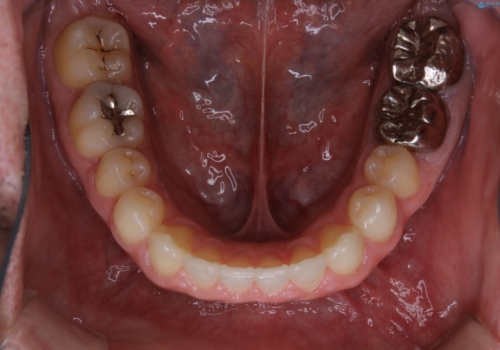

- 全体的に歯と歯の間に隙間があるのが気になるとのことで来院されました。インビザラインでの矯正治療をご希望されました。

隙間については、前歯と奥歯に多数あります。また、上下前歯は、外側に少し倒れているため隙間を閉じつつ、前歯を内側に引っ込めて並べることになりました。

インビザライン・ライトにて矯正治療を行うことになりました。